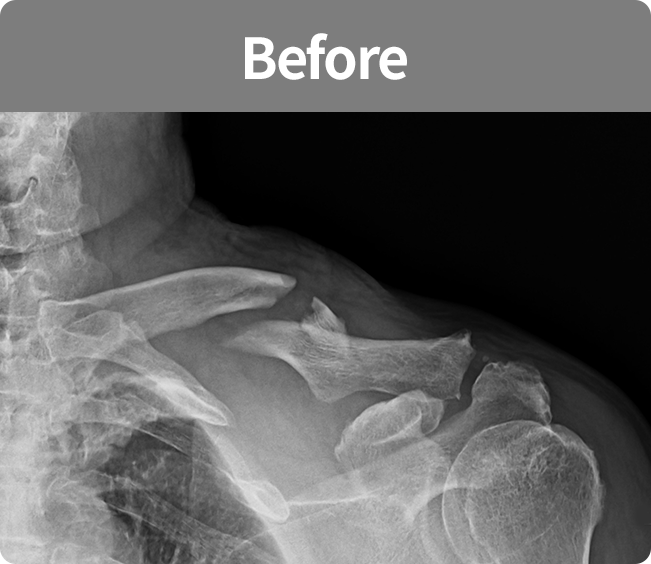

회전근개 봉합술

어깨뼈와 회전근개 힘줄이 충돌로 인하여 나타나는 염증 등을 관절경을 이용하여

견봉 부위의 염증 부위를 치료하고 견봉 부위의 마모로 인하여 거칠어진 부분을 넓게 확보해주는 수술법